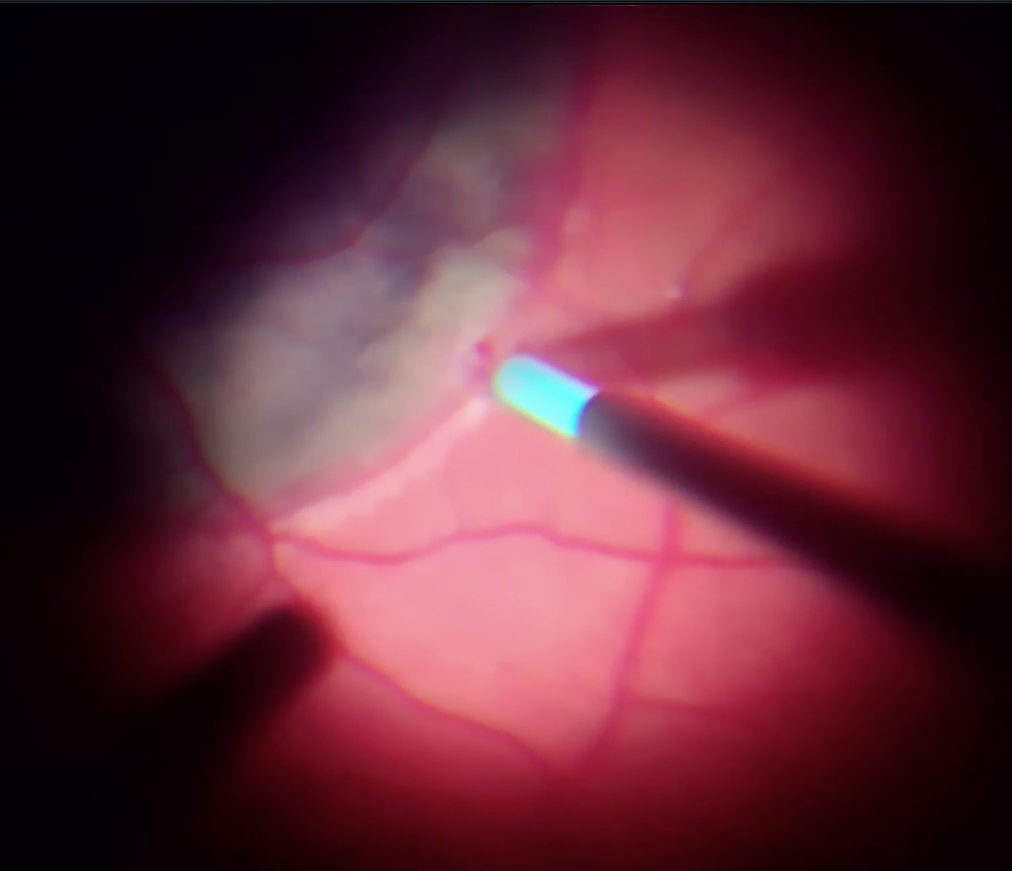

В операційній перше, що привернуло увагу - це щільна адгезія скловидного тіла до сітківки, але це питання було вирішено вітреотомом та кеналогом.

Після діатермії було виконано дренуючу ретинотомію на межі крововиливу (можна було би ще ближче до центру, але не хотілося потім виконувати лезеркоагуляцію поблизу до СНМ) та частково роздреновано субретинальній простір.

В подальшому з використанням пухиря ПФОС на сітківці та пухиря стерильного повітря під сітківкою виконано розрідження та дислокація субретинального крововиливу з аспірацією рідкого гему крізь дренуючу ретинотомію.